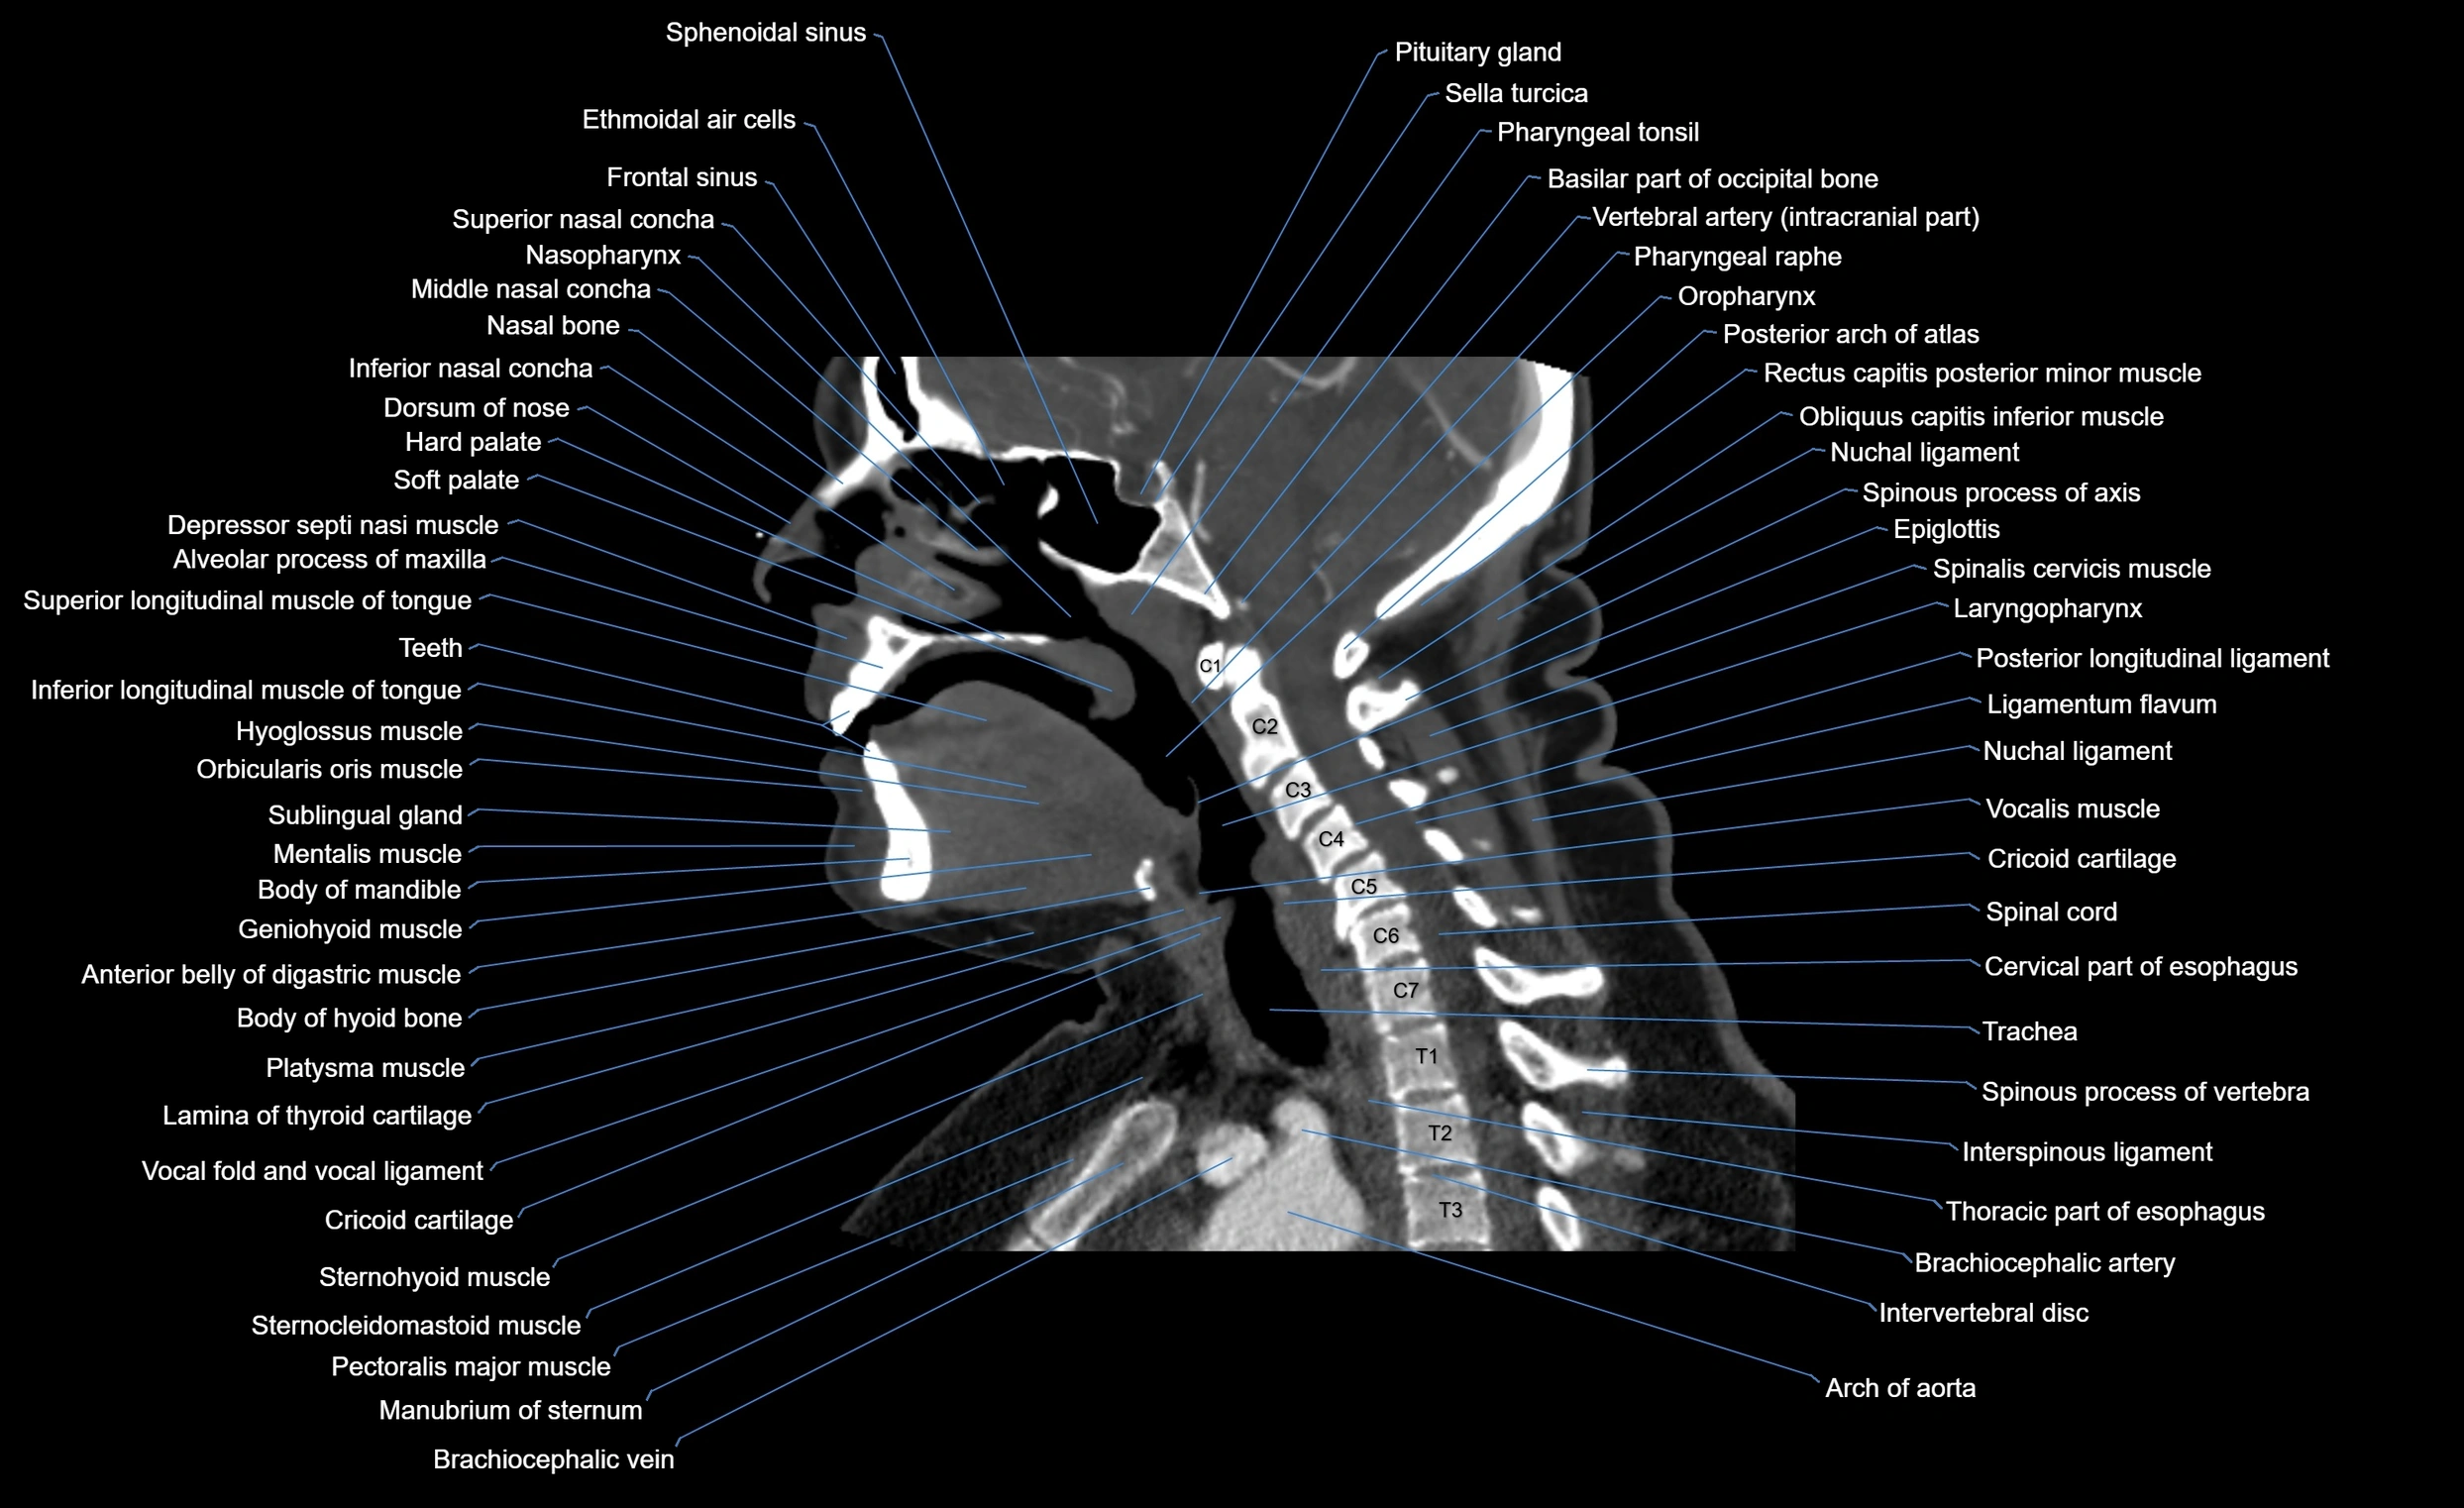

- Anterior belly of digastric muscle

- Cervical part of esophagus

- Epiglottis

- Inferior nasal concha

- Interspinous ligament

- Intervertebral Disc

- Laryngopharynx

- Ligamenta flava (Ligamentum flavum)

- Posterior longitudinal ligament

- Soft palate

- Spinal cord

- Thoracic part of esophagus

- Trachea

- Vocalis muscle